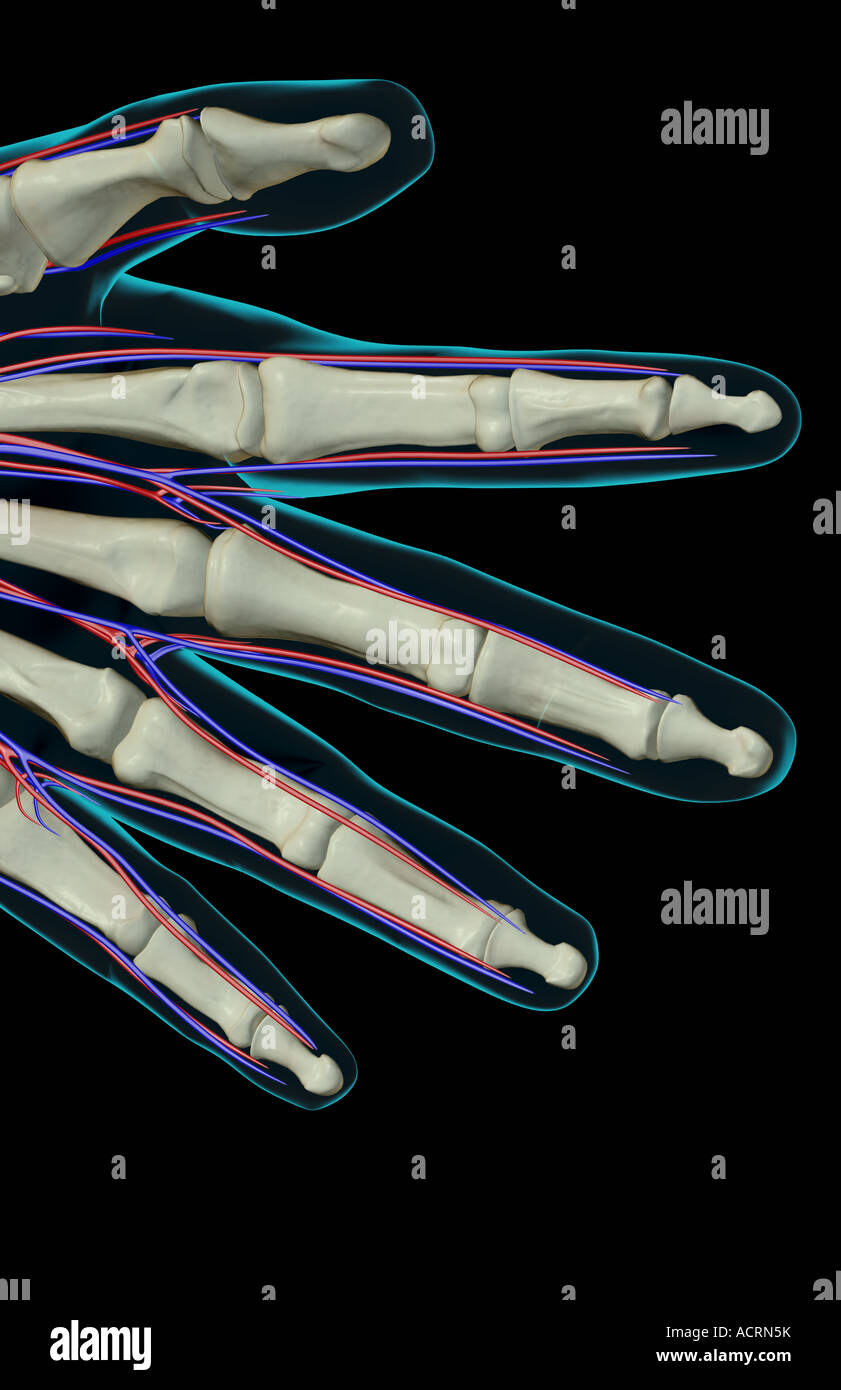

The blood supply of the fingers Stock Photohttps://www.alamy.com/image-license-details/?v=1https://www.alamy.com/stock-photo-the-blood-supply-of-the-fingers-13219086.html

The blood supply of the fingers Stock Photohttps://www.alamy.com/image-license-details/?v=1https://www.alamy.com/stock-photo-the-blood-supply-of-the-fingers-13219086.htmlRFACRN5K–The blood supply of the fingers